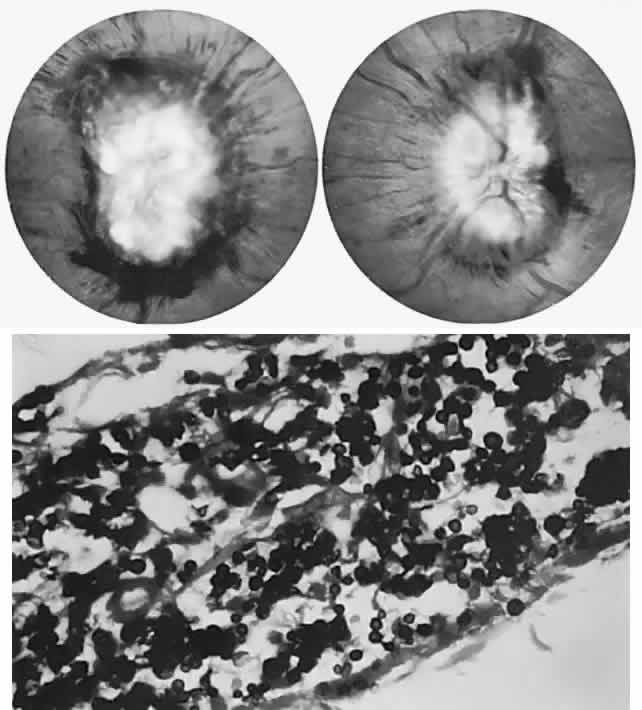

The ganglion cell layer of the retina is a principal site of abnormal accumulation of anomalous storage products, such that ophthalmoscopic changes are observable either in the form of retinal “graying” or the well-known cherry-red spot. The ganglion cell layer densely surrounds the thin fovea, which transmits the normal red color of underlying choroid (Fig. 4). The storage disorders with cherry-red spot or macular graying are listed in Table 2.27

Fig. 4. “Cherry-red spot” of advanced Tay-Sachs disease (gangliosidosis). Note the central foveal window surrounded by a ring of densely opaque retinal ganglion cell layer; also, optic atrophy.